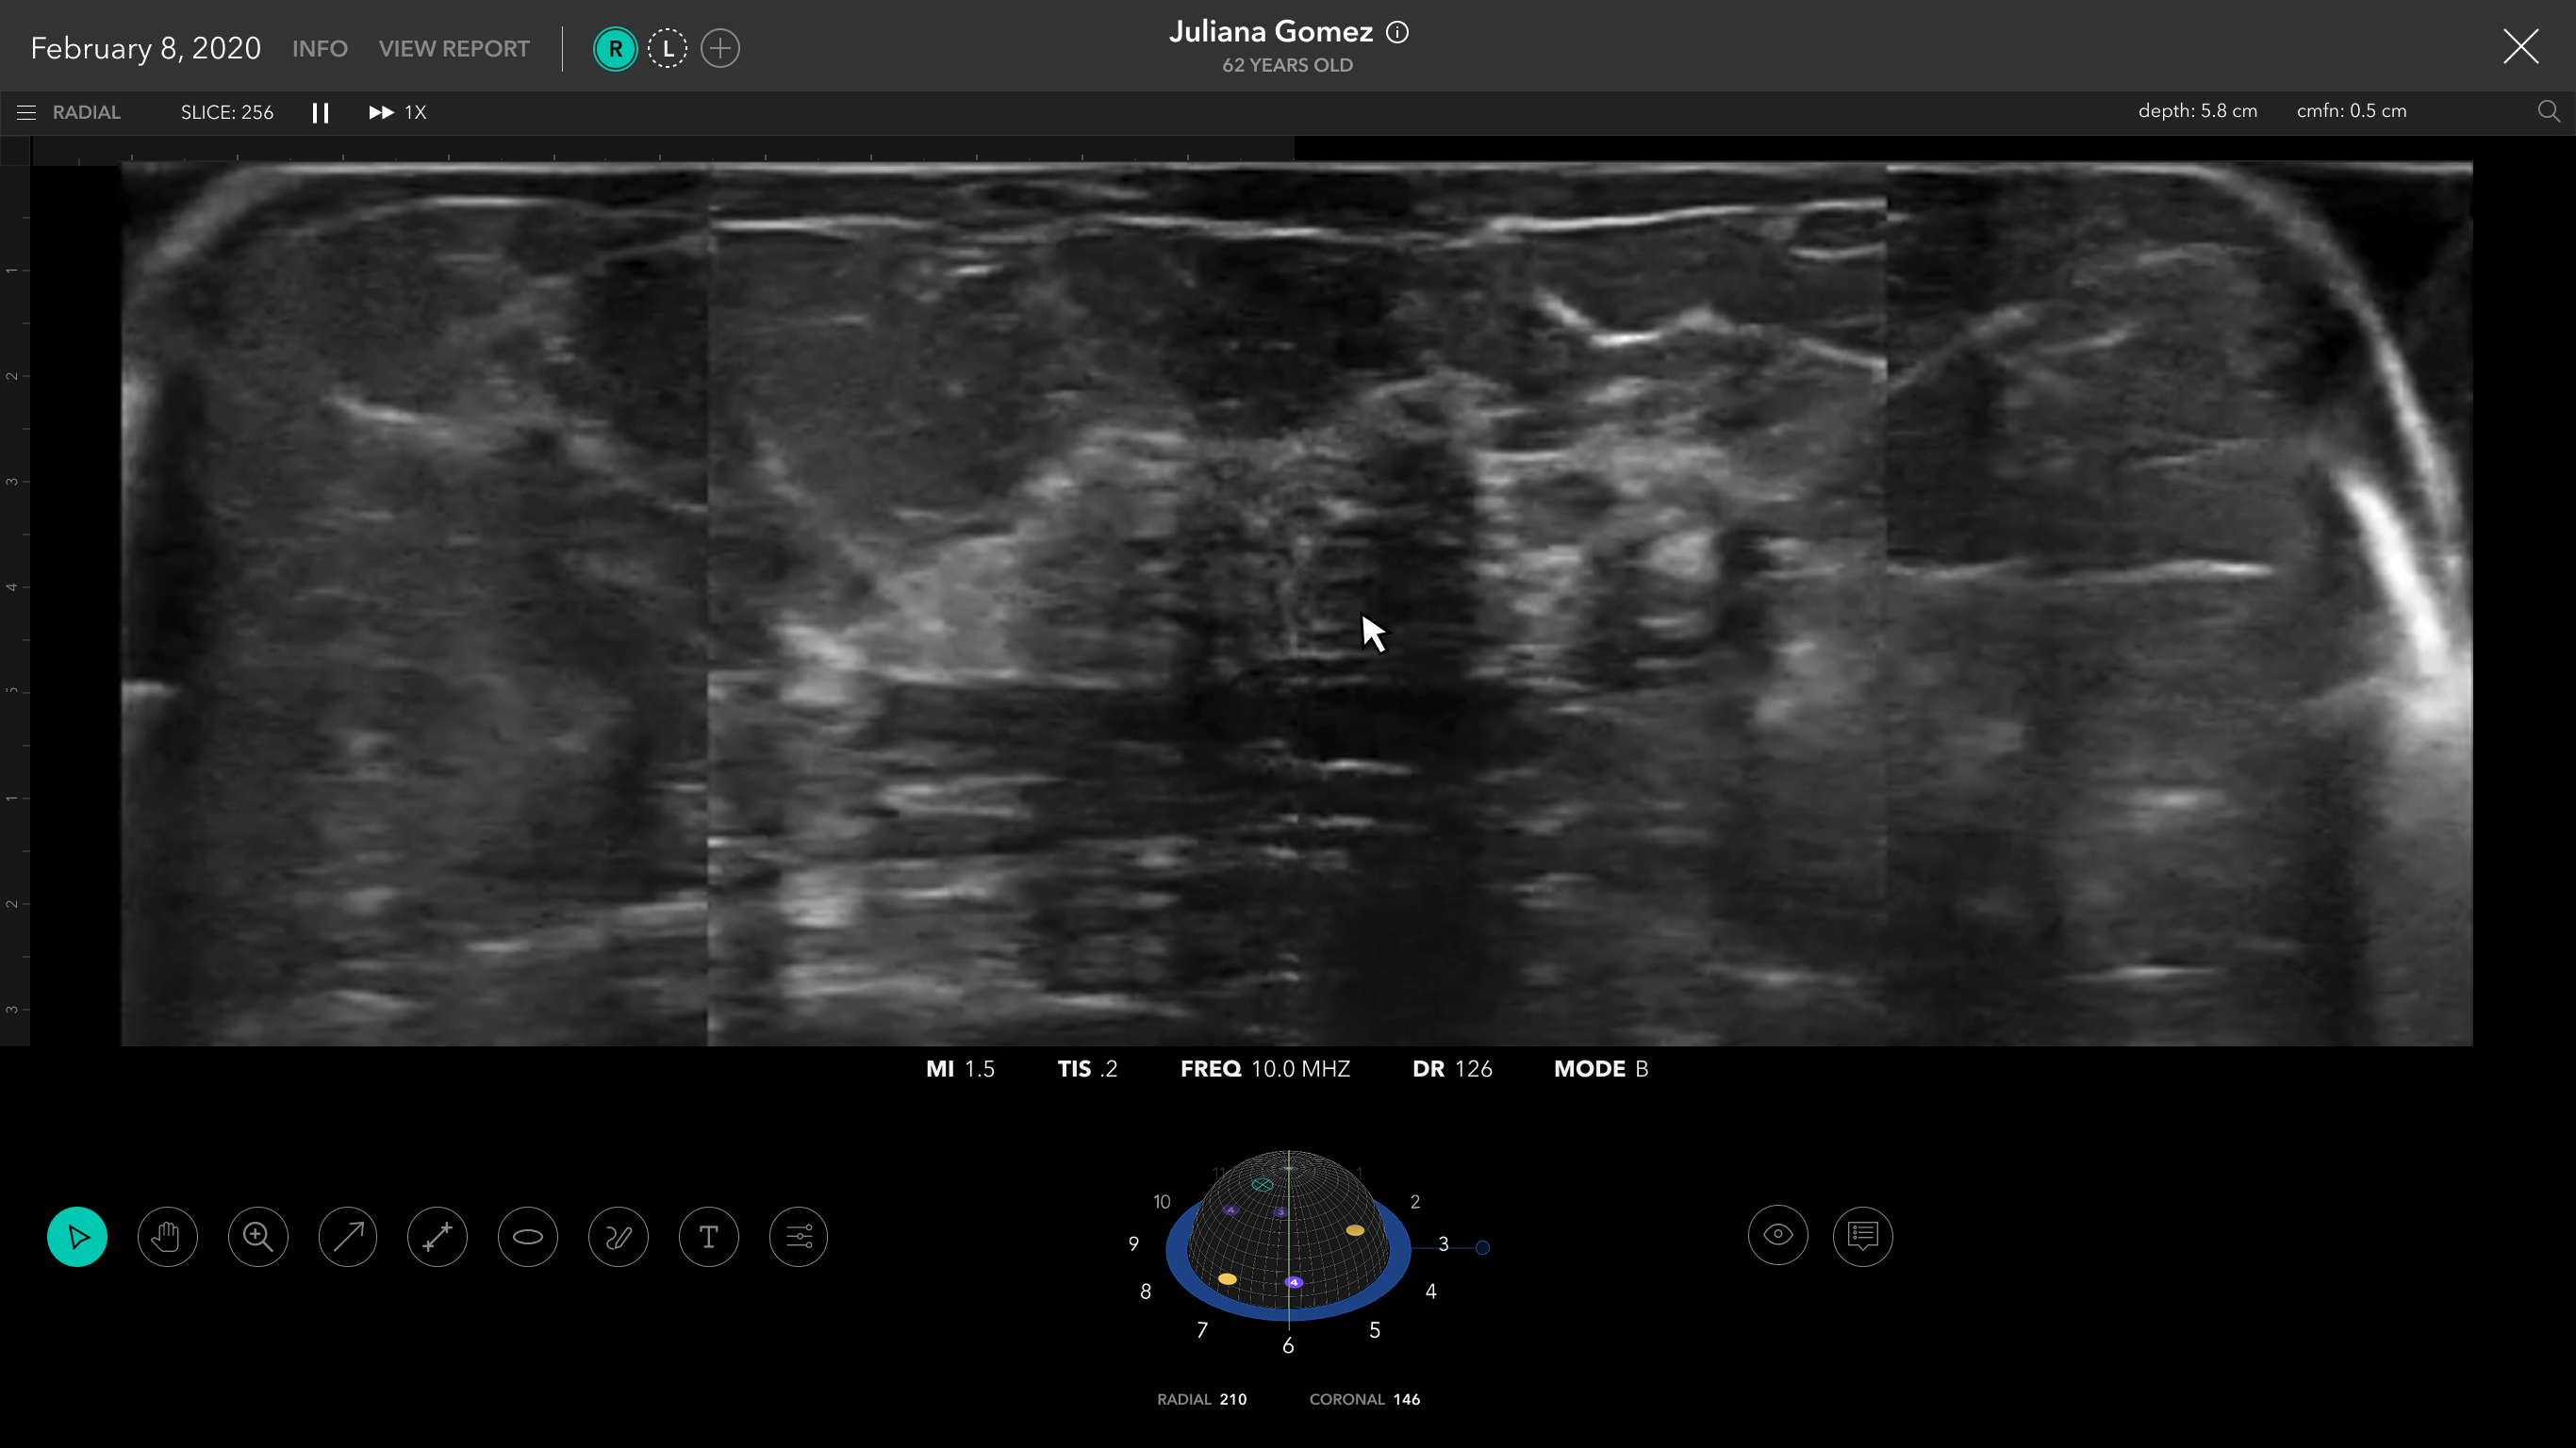

I helped design an AI-driven software application for breast imaging.

The wearable scanner automatically captures the entire breast volume allowing for repeatable breast imaging at point of care.

Scan Flow